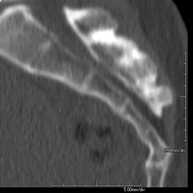

- TC Oídos Prueba radiológica que consiste en obtener imágenes del oído de alta definición anatómica (conducto auditivo interno y externo, tímpano, huesecillos del oído), mediante el empleo de un equipo de TC (Tomografía Computarizada). Indicaciones: trastornos de la audición, cuadros vertiginosos, mareos, acúfenos (pitidos). Prueba radiológica que consiste en obtener imágenes del oído de alta definición anatómica (conducto auditivo interno y externo, tímpano, huesecillos del oído), mediante el empleo de un equipo de TC (Tomografía Computarizada). Indicaciones: trastornos de la audición, cuadros vertiginosos, mareos, acúfenos (pitidos).

- TC Peñascos Prueba radiológica que consiste en obtener imágenes del hueso peñasco del temporal (oído interno, medio y externo) de alta definición anatómica mediante el empleo de un equipo de TC (Tomografía Computarizada). Indicaciones: pérdida de audición súbita o crónica, cuadros vertiginosos, mareo, malformaciones congénitas. Prueba radiológica que consiste en obtener imágenes del hueso peñasco del temporal (oído interno, medio y externo) de alta definición anatómica mediante el empleo de un equipo de TC (Tomografía Computarizada). Indicaciones: pérdida de audición súbita o crónica, cuadros vertiginosos, mareo, malformaciones congénitas.